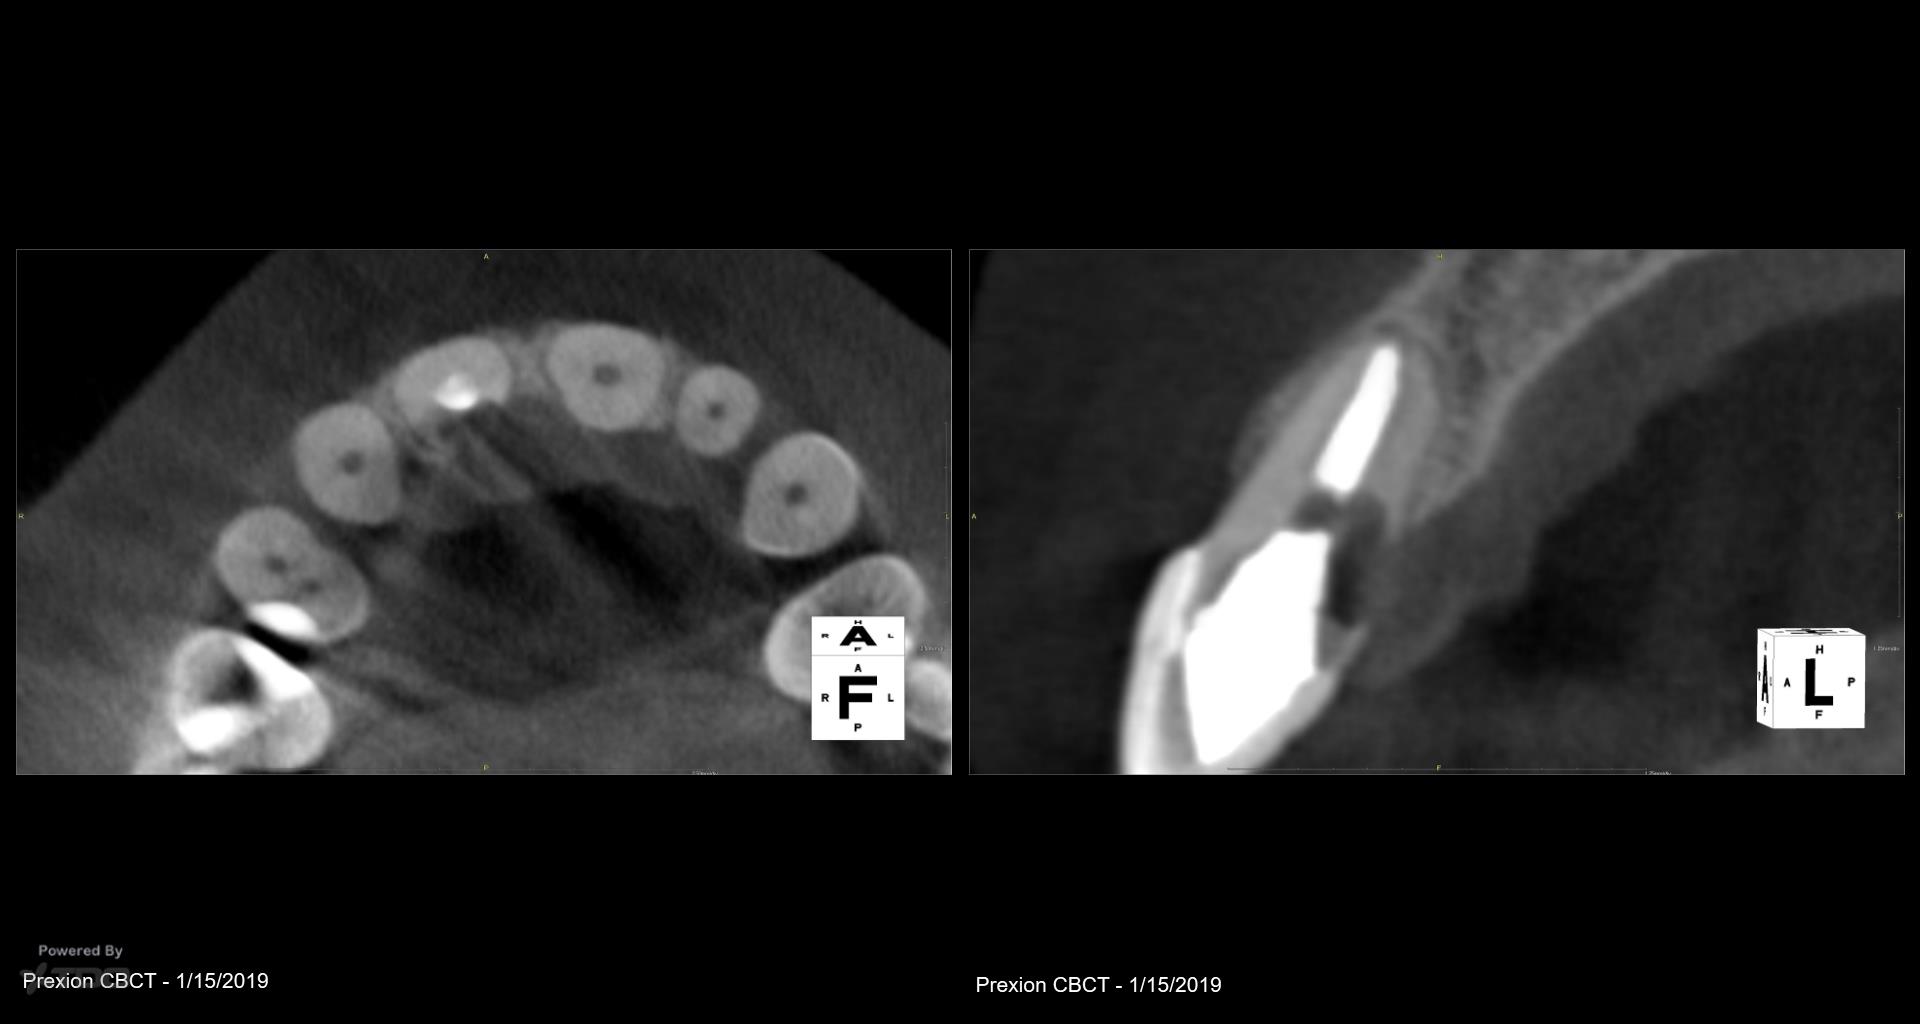

I did this RCT 34 years ago when the patient was 14. Now there is a parulis and lingual palpation sensitivity. Extract or treat? Patient has a very high smile line, thin biotype, is sensitive to costs. gbc

What is the treatment option being considered? Can you flap and repair? The lesion appears well-demarcated, without bone ingrowth, so it may be a simple repair with minimal ostectomy. If the patient can tolerate a couple black triangles (despite only flapping the palatal), then I might do it.